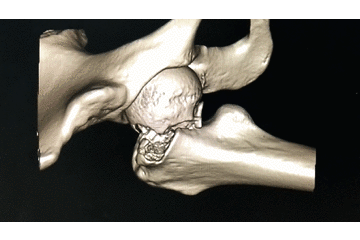

辅助检查:CT 检查提示右侧股骨颈骨皮质不连续,可见透亮骨折线及碎骨片影,断端错位、成角,周围软组织肿胀;右侧髋臼后下缘及左侧耻骨上支骨皮质不连续,断端未见明显错位;右侧髋臼后缘见类圆形稍低密度影,大小约 5*9 mm,边界清楚,边缘见硬化边;右侧髋关节在位,关节间隙未见明显变窄。

初步诊断:右股骨颈骨折(经颈型)